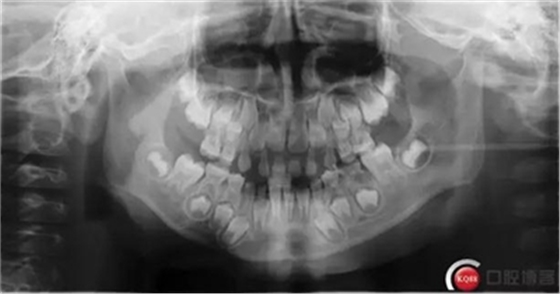

檢查:*75殘冠穿通髓腔,質(zhì)軟,叩診(++),溫度測(cè)試無(wú)反應(yīng),X線顯示遠(yuǎn)中根已完全吸收、近中根吸收至根頸1/3,且根尖可見低密度暗影。

診斷:*75牙體缺損+根尖周炎